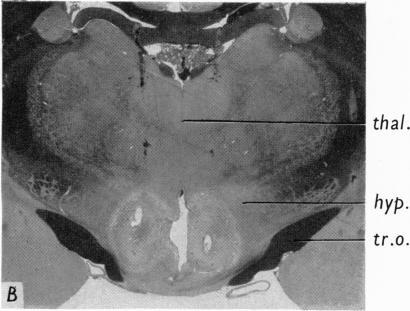

Organization of the subcortical system governing defence and flight reactions in the cat.

J Physiol. 1962 Feb;160(2):200-13. doi: 10.1113/jphysiol.1962.sp006841.